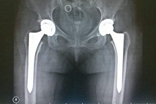

擅長:類風(fēng)濕關(guān)節(jié)炎、骨關(guān)節(jié)炎、強(qiáng)直性脊柱炎、股骨頭壞死、髖發(fā)育不良、血友病性關(guān)節(jié)炎、痛風(fēng)性關(guān)節(jié)炎等各種髖、膝復(fù)雜病例的人工關(guān)節(jié)置換。在感染、無菌性松動(dòng)、假體周圍骨折等原因?qū)е碌娜斯りP(guān)節(jié)翻修手術(shù)方面經(jīng)驗(yàn)豐富,治療水平國內(nèi)領(lǐng)先。

置換人工關(guān)節(jié)后千萬別忽視小傷口置換人工關(guān)節(jié)后,病人應(yīng)該重視發(fā)燒、拔牙等可能造成血源性感染以及骨折等情況。[詳細(xì)]

置換人工關(guān)節(jié):解決疼痛 恢復(fù)功能是否要做手術(shù),首先看年齡。其次要衡量實(shí)際疼痛,以行走能力來判斷,如果走不了500米,說明疼得比較重。最后,能不能伸直是判斷關(guān)節(jié)變形嚴(yán)重程度的指標(biāo)。[詳細(xì)]